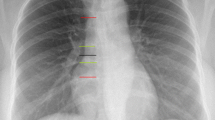

Study Outcome Measurements

Correct PICC tip position was defined as within the mid to lower superior vena cava, at the level of the cavoatrial junction, or within the upper portion of the right atrium, corresponding to 1.5 vertebral body units (approximal 3 cm) from the tracheal carina on chest X-ray obtained immediately after insertion. Time for PICC insertion started from introduction of the guidewire into the vein and ended with stabilization of the catheter on the arm. In order to assess catheter-related complications, patients were followed up within 2 weeks after PICC insertion. Patients were considered lost to follow up at withdrawal of the catheter.

Incidence of correct PICC tip position was 82.4% (84 of 102) in the TCS group and 99.0% (103 of 104) in the fluoroscopy group. The lower bound of a one-sided 95% confidence interval (CI) of −23.1% difference in proportions of proper tip position was below the prespecified boundary of −5%. Thus, noninferiority of TCS compared to fluoroscopy was not established (p value for noninferiority: > 0.99). The two-sided 95% CI was entirely below the noninferior margin, and therefore demonstrated inferiority of TCS over fluoroscopy (−16.7% [95% CI −24.3 to −9.1%], p < 0.001) (Fig. 3). Logistic regression revealed an increased odds for malposition in obese patients (odds ratio 2.9 [95% CI 1.1 to 7.9], p = 0.04). However, age, sex, and BMI did not interact with the effect of TCS (Fig. 3). Five of 18 cases of incorrect tip position in the TCS group (27.8%) were associated with a weak signal of the TCS. In 12 of 17 cases of weak TCS signal, a correct tip position was achieved based on ECG guidance alone. Weak signal was not significantly associated with obesity (odds ratio 1.3 [95% CI 0.4 to 4.6], p = 0.67).